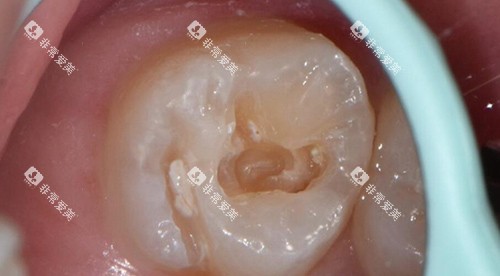

损伤程度:浅龋直接填充费用低,深龋需先做根管治疗再修复,总费用翻倍;

深龋修复:根管治疗+牙冠修复

根管治疗费用

前牙:240元-500元起/颗

后牙:800元-1200元起/颗

特点:后牙根管数量多、操作难度大,费用显著高于前牙。